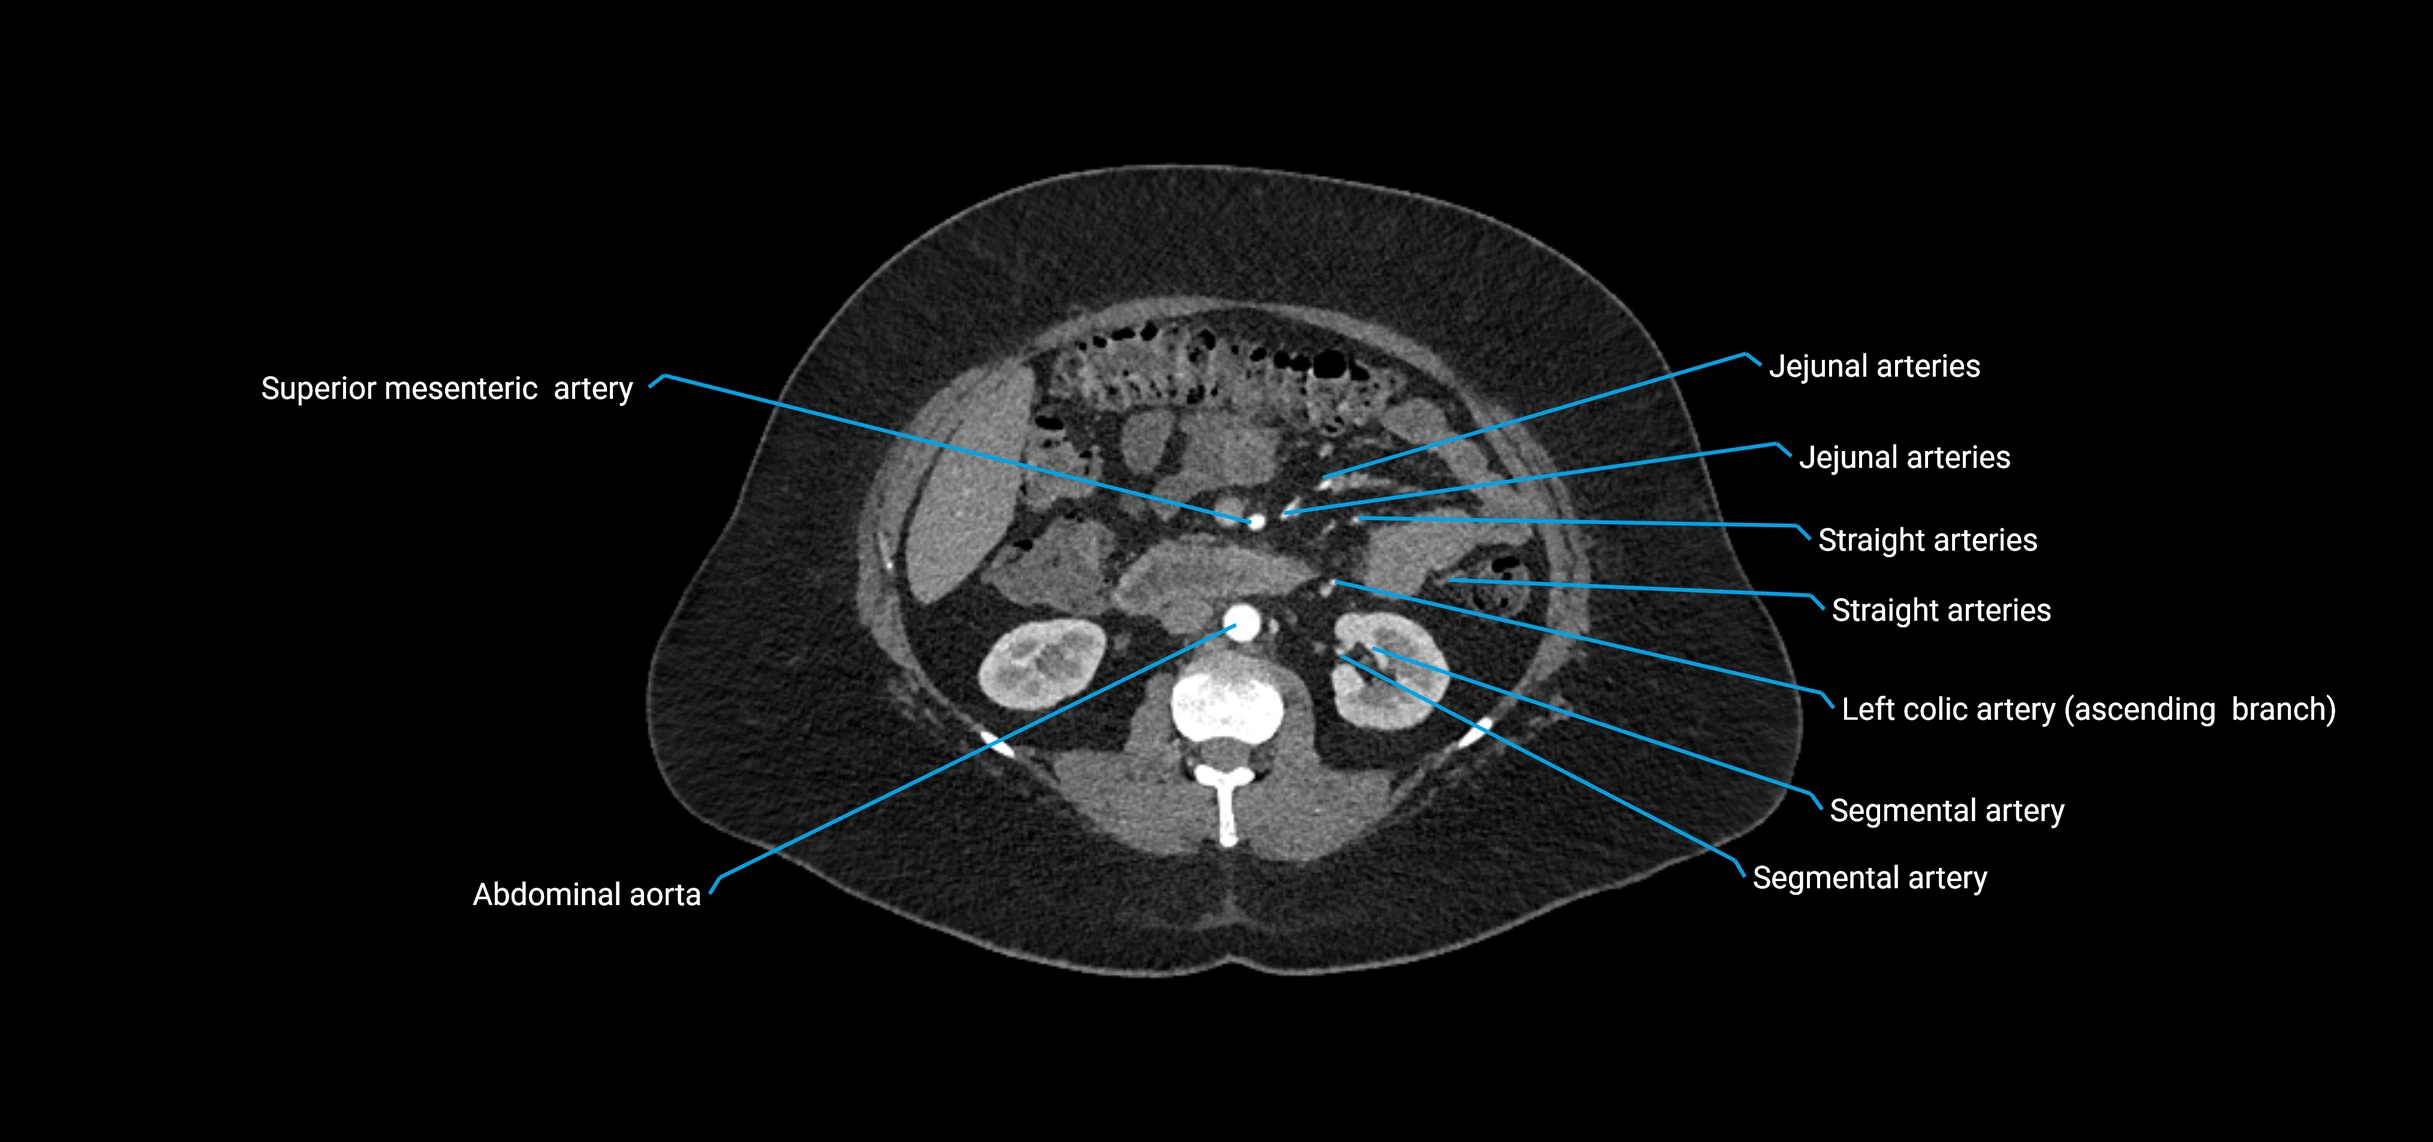

CT images

image

Contrast-enhanced CT (CTA):

• Gold standard for abdominal aortic imaging

• Provides excellent detail of lumen, wall, aneurysm, thrombus, and branch vessels

• Multiplanar and 3D reconstructions help in aneurysm measurement, stent graft planning, and dissection evaluation

• Unpaired visceral branches: celiac trunk, superior mesenteric artery (SMA), inferior mesenteric artery (IMA)